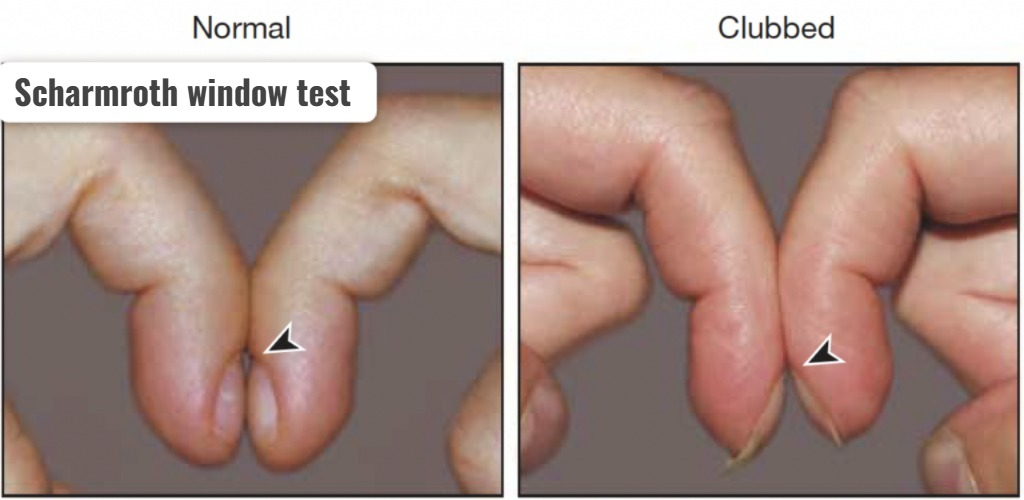

Scharmroth window test (સ્કાર્મરોથ વિન્ડો ટેસ્ટ):

- સ્કાર્મરોથ વિન્ડો ટેસ્ટ એ ફિંગર માં ક્લબિંગ પ્રેઝન્ટ છે કે નહીં તે કન્ફર્મ કરવા માટે વપરાય છે.

- સ્કાર્મરોથ વિન્ડો ટેસ્ટમાં પિક્ચરમાં દર્શાવ્યા મુજબ બંને હાથની એક એક આંગળીના નેઇલ બેડને સાથે રાખવામાં આવે છે અને નેઇલ બેડની વચ્ચે ડાયમંડ શેપ જોવા મળે છે કે નહીં તે ચેક કરવામાં આવે છે.

- જો નેઇલ બેડની વચ્ચે ડાયમંડ શેપ જોવા મળે તો તે નોર્મલ છે જ્યારે નેઇલબેડની વચ્ચે સ્પેસ જોવા ન મળે તો તે ક્લબિંગ ઇન્ડિકેટ કરે છે.